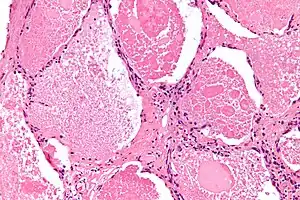

Lung washings or tissue for histopathologic analysis are most commonly obtained using bronchoalveolar lavage and/or lung biopsy.[12] Characteristic biopsy findings show filling of the alveoli (and sometimes terminal bronchioles) with an amorphous eosinophilic material, which stains strongly positive on PAS stain and the PAS diastase stain. The surrounding alveoli and pulmonary interstitium remain relatively normal.[13] Electron microscopy of the sample, although not typically performed due to impracticality, shows lamellated bodies representing surfactant.[14] An alternative diagnosis with similar histomorphologic findings is Pneumocystis jirovicii pneumonia.[14]

Lung washings characteristically yield a fluid which is "milky"composition. Under the microscope, samples show 20-50 micrometer PAS-positive globules on a background of finely granular or amorphous PAS-positive material. There is typically a low numbers of macrophages and inflammatory cells (although this is variable).[13][14]